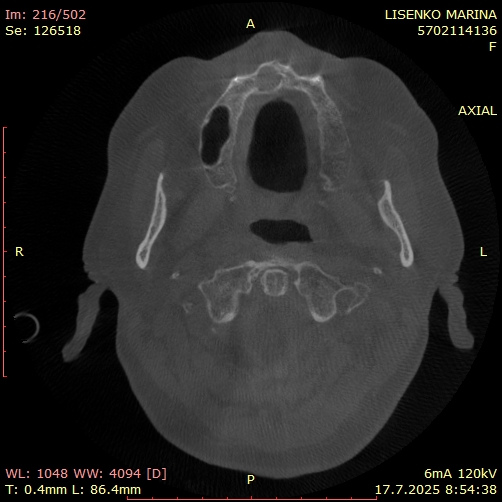

Axial срез от КБКТ, показващ киста в областта на назопалатиналния канал